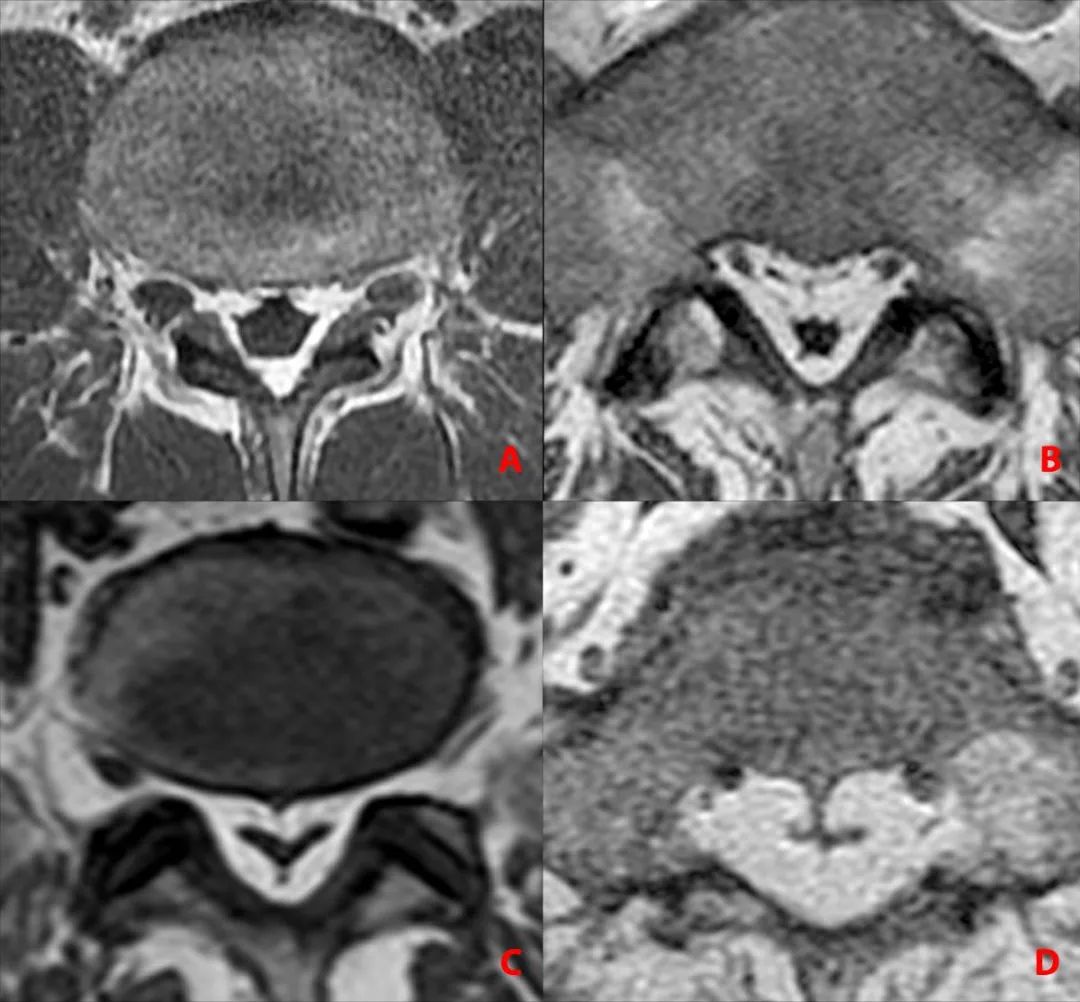

轴面上 T2WI 收到硬膜外脂肪的推挤,硬膜囊可以发生变形(正常为椭圆形)通常为多边形(A)、星状(B)或 Y 形或 V 形(C-D)

SEL 的硬膜外脂肪沉积通常是左右对称的,更罕见的是,它是不对称的。此处,大家会考虑红箭头所示的条样低信号是什么呢?

腰椎管横切面显示:硬膜外间隙存在硬脊膜椎韧带,正中(A 中的箭头)、双侧旁正中(B 中的箭头)和外侧(C 中的箭头),向后牵拉硬膜囊(S:塌陷的硬膜囊)

硬脊膜椎韧带向前牵拉硬膜囊(S:塌陷的硬膜囊)

硬脊膜椎韧带的分布也存在变异,数字代表在各个方向出现的频率

那么绿箭头所示的其实是硬脊膜椎韧带